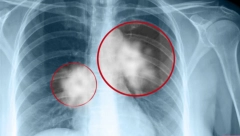

Tema: astma

DECA SVE VIŠE OBOLEVAJU OD ASTME Više od 300 miliona ljudi u svetu ima jednu od najčešćih hroničnih bolesti

NOVI LEK ZA ASTMU STIGAO U SRBIJU Mogao bi da promeni život mnogim obolelima

NOVI LEK ZA ASTMU U POSLEDNJIH 50 GODINA Još je u fazi ispitivanja, ali daje odlične rezultate

REVOLUCIONARNI LEK ZA ASTMU Prvi u poslednjih 50 godina dobio takvu ocenu

IZNENADA UMRLA INFLUENSERKA (25) Imala bolest od koje u Srbiji pati oko 220.000 ljudi

GOJAZNOST I CIGARE KOBNE ZA ASTMATIČARE! Direktor Klinike za pulmologiju o prevenciji bolesti

Ako se ne leči, dovodi do teških poremećaja: Pulmolog otkriva koje astma simptome nikako ne smemo da ignorišemo

PULMOLOG UKCS: ZBOG OVE TRI STVARI SVE VIŠE LJUDI U SRBIJI BOLUJE OD ASTME! Prekinite sa ovim odmah!

SVE VIŠE LJUDI U SRBIJI IMA OVU BOLEST Simptomi su podmukli, a dr Stjepanović upozorava koji je najopasniji i kada je vreme za lekara